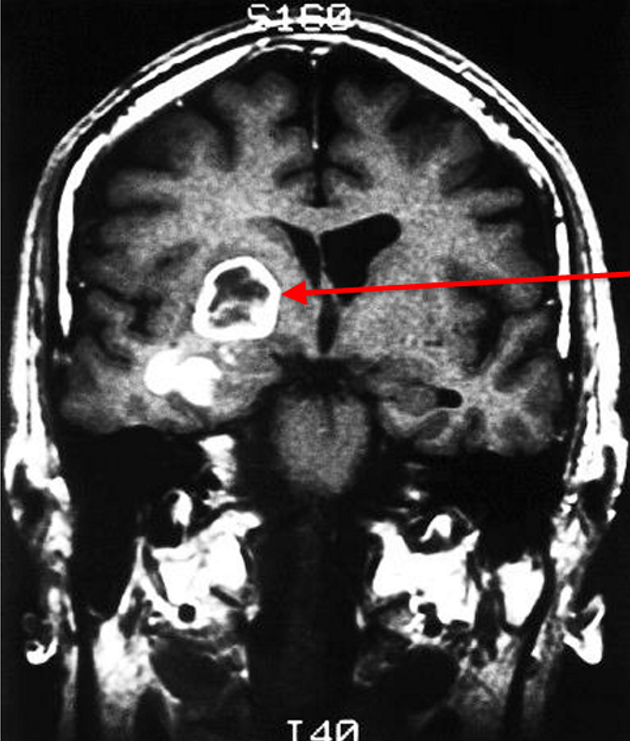

Glioblastoma

(definition + signs + diagnosis)

Grade IV astrocytoma

Diagnosis

CT shows ring-like contrast enhancement aginst central necrosis

Biopsy shows pleomorphism, high cellularity and infiltration of tumour cells, palisaded necrosis and microvascular proliferation